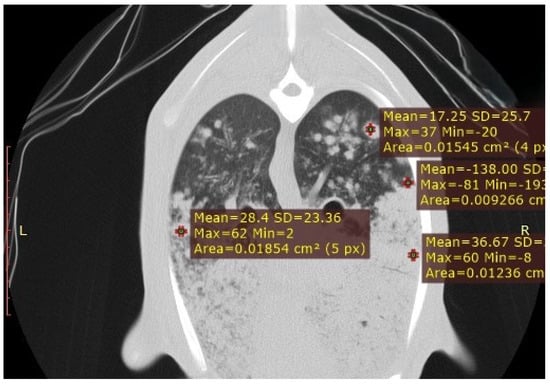

3.3.1. Interstitial Pneumonia (SRLV)

| SRLV | Diffuse, entire lung parenchyma | 800 to −400 HU | Severity-dependent: mild (−700 to −800 HU), moderate (−550 to −700 HU), severe (−400 to −550 HU); reflects cellular infiltration |